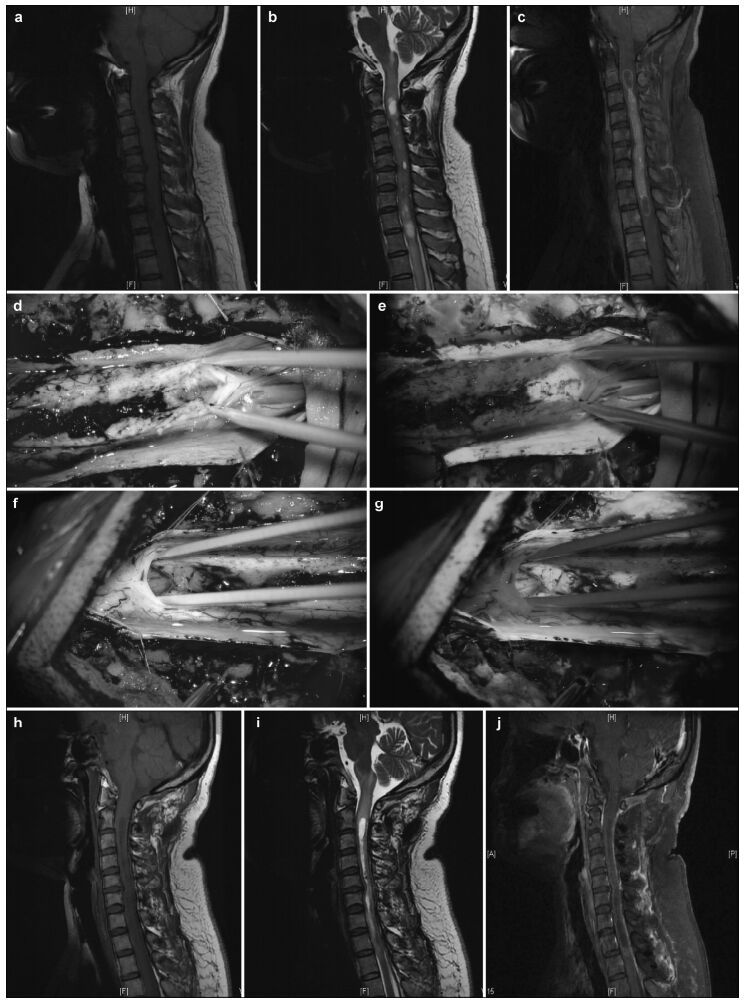

| Figure 1 Pre-and postoperative magnetic resonance imaging of intramedullary ependymomas at C1-T1, and intraoperative observations. (a) Preoperative sagittal T1 image reveals spinal cord thickening. (b) T2 image shows high intramedullary signal intensity at C1-T1, but no signal at either end. (c) Enhanced scanning reveals distinctive tumor enhancement. (d) Intact tumor with clear boundaries, as viewed under a microscope. (e) Tumor images, viewed via fluorescence microscopy, showing a distinctive basal structure. Sagittal T1 (f) and T2 (g) images, 3 months after surgery, do not show tumor residuals or relapses. |

3 Results 3.1 Intraoperative tumor statusIn the absence of FS, 80 patients demonstrated clear tumor boundaries and 32 had blurry tumor boundaries resulting from tumor adhesion to the spinal cord, including 14 with severe adhesions and intramedullary tumor-associated strokes (Figures 1-3). Under fluorescence, tumors were visible in 94 patients and invisible or indistinct in 18, including 14 with intramedullary tumor-associated strokes and indistinct MRI enhancement and four without MRI enhancement. Under fluorescence, complete tumor removal was accomplished in 92% (103/112) of the patients. Of the nine patients with tumors that could not be completely removed, five had myxopapillary ependymomas at the conus medullaris and four also had strokes and severe adhesions.